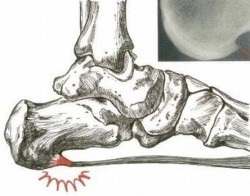

calcaneu pinten

toc pinteni - cele mai frecvente cauze, provoacă dureri în călcâi

Sentimentul de piroane în călcâi să sape o sarcină pe picior, durere severă - plângerile obișnuite la Heel grăbi. Boala apare ca o acumulare de tesut osos, adesea însoțită de depunerea de săruri. procese inflamatorii. Aceasta poate să apară ca o boală independentă și separat, dar cel mai adesea este o consecință a bolilor mai complexe.

Excrescență dezvoltă adesea pe fundalul guta sau artrita: sare stivuirea ca durata bolii, cauzând proliferarea. Uneori, o persoană poate simți o ușurare puternică, reducerea intensității durerii, la momentul în care impulsul este pe deplin format. Natura durerii în călcâi se schimbă dureros de a merge singur, după o noapte de somn.

Cauzele durere în călcâi devine pantofi cu toc înalt, situația se înrăutățește în cazul în care flatfoot severă pacientului. sarcină grea pe picioare - prima instalare a unui provocator. Această sarcină este, de obicei, se confruntă persoanele cu greutate mai mult din cauza distribuției greutății necorespunzătoare. În caz de rănire sau vătămare poate apărea, de asemenea, în pintenul.

pantofi incomode contribuie la apariția durerii călcâi

Se determină prezența sa este posibilă numai cu ajutorul razelor X. Dar ține cont de faptul că simpla existență a unei proliferare pinten osos nu înseamnă că oamenii pot trăi de ani de zile si nu se simte durere și disconfort. Acesta poate fi opusul: nici o deformare a osului, dar durerea în picior și toc nu dau să meargă. De asemenea, trebuie să acorde o atenție la exact în cazul în care există durere, deoarece acest lucru poate indica sursa de apariție a durerii în picior.